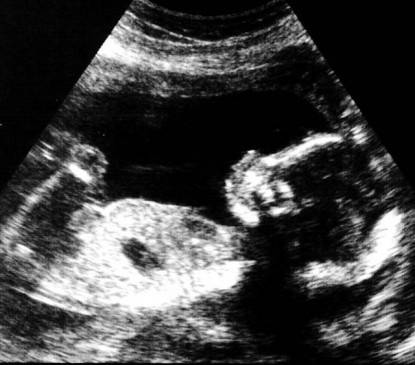

Fanno le facce. Osservando ecografie fatte in 4D i medici della Durham University hanno visto che dalla ventiquattresima settimana i bambini possono assumere due espressioni facciali simili a un sorriso. Dalla trentaseiesima invece possono esprimere facce più complesse come ciglia corrucciate, naso arricciato e bocca tesa.